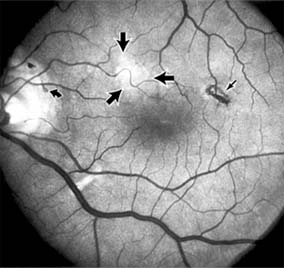

CENTRAL SEROUS CHORIORETINOPATHY

Central serous chorioretinopathy is characterized by serous detachment of the sensory retina as a consequence of focal leakage of fluid from the choriocapillaris through a defect in the retinal pigment epithelium (Figures 10-2 and 10-3). This disease typically affects young to middle-aged men and may be related to life stress events. Most patients present with the sudden onset of blurred vision, micropsia, metamorphopsia, and central scotoma. Visual acuity is often only moderately decreased and may be improved to near-normal with a small hyperopic correction.

Figure 10-2

Figure 10-2: Central serous chorioretinopathy with sensory retinal detachment (arrows) extending into the fovea.

Figure 10-3

Figure 10-3: Fluorescein angiogram of central serous chorioretinopathy shows active disease with both a retinal pigment epithelial detachment (small arrows) and a sensory retinal detachment (large arrows). Two foci of inactive disease (open arrows) are also present.

The diagnosis is made by slitlamp examination of the fundus; the presence of serous detachment of the sensory retina in the absence of ocular inflammation, subretinal neovascularization, an optic pit, or a choroidal tumor is diagnostic. The retinal pigment epithelial lesion appears as a small, round or oval, yellowish-gray spot that is variable in size and may be difficult to detect without the aid of fluorescein angiography. Fluorescein dye leaking from the choriocapillaris may accumulate below the pigment epithelium or sensory retina, resulting in a variety of patterns including the well-recognized smokestack configuration.